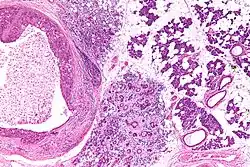

| Low magnification micrograph of a salivary duct carcinoma with characteristic comedonecrosis (left of image) adjacent to normal parotid gland (right of image). H&E stain. | |

Their histologic appearance is similar to ductal breast carcinoma.